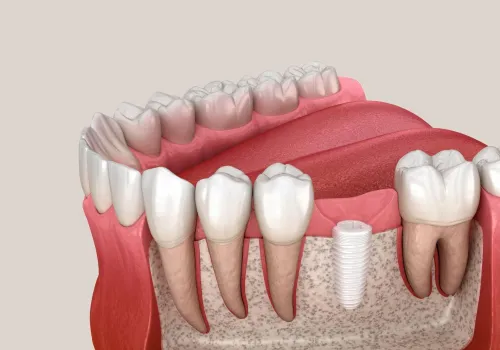

Der Vorteil des ALL-ON-4® Verfahrens liegt darin, dass mit nur 4 miteinander verbundenen Implantaten pro Kiefer eine festsitzende Brücke direkt nach dem Entfernen der nicht mehr erhaltungswürdigen Zähne eingesetzt werden kann. In der Regel kann auf eine provisorische Versorgung verzichtet werden, was dem Patienten erhebliche Kosten für den provisorischen Zahnersatz (ca. 1500 CHF pro Kiefer) spart.

Die Implantate für das ALL-ON-4® Verfahren bestehen, wie herkömmliche Implantate, aus hochreinem Titanoxid, das auch für Knie- und Hüftprothesen verwendet wird. Dieses Material ist äusserst biokompatibel, sehr belastbar und hervorragend verträglich.

Die auf den Implantaten verschraubten Brücken bestehen aus einem präzisionsgefertigten Titan- oder Vollkeramikgerüst und sind mit natürlich aussehenden Keramikzähnen ausgestattet.